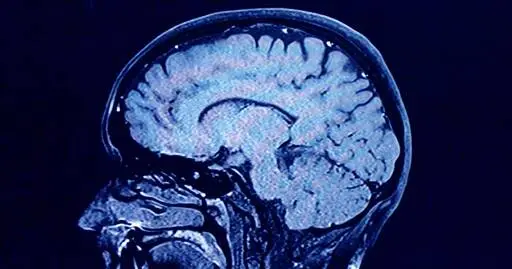

As we age, the human brain rewires itself. The process happens in distinct phases, or “epochs,” according to new research, as the structure of our neural networks changes and our brains reconfigure how we think and process information.

For the first time, scientists say they’ve identified four distinct turning points between those phases in an average brain: at ages 9, 32, 66 and 83. During each epoch between those years, our brains show markedly different characteristics in brain architecture, they say.